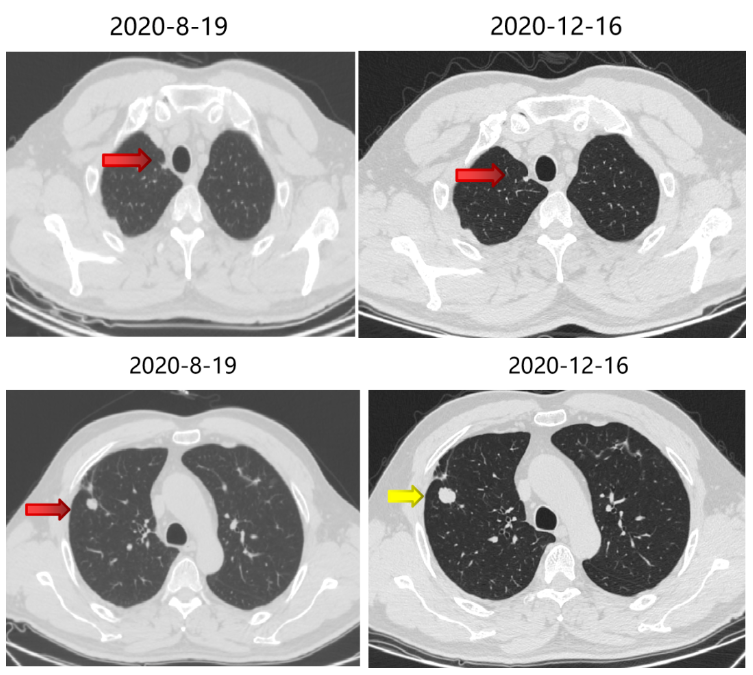

局部治疗(二):SBRT治疗

2020-11-6至2020-11-25 左肺下叶及右肺下叶转移灶放疗:95% PTV1-2 74.7Gy/4.98Gy/15F。

2020-12-31至2021-1-19右肺上叶转移灶放疗:95% PTV 74.7Gy/4.98Gy/15F。

SBRT疗效评价:部分缩小。